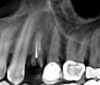

(12.) Postoperative CBCT image of actual implant placement at site No. 21.

Figure 12

(13.) Postoperative CBCT image of actual implant placement at site No. 19.

Figure 13

A healthy 60-year-old female presented for an emergency evaluation because she was experiencing pain associated with tooth No. 20. It was mobile, malposed, and given a diagnosis of irreversible pulpitis. In addition, teeth Nos. 19 and 21 had been missing for more than 5 years. After the evaluation, a discussion revealed that the patient desired implant reconstruction of the lower left quadrant. During this initial visit, a CBCT scan was obtained, and the virtual restoration-driven implant planning was completed, confirming that extraction of tooth No. 20 with robot-assisted immediate implant placement at the sites of teeth Nos. 19 and 21 was a viable option (Figure 9 through Figure 13). Splint placement, CBCT capture of the fiducial array, calibration, and landmark confirmation were completed as described in the first case report. Following the administration of intravenous sedation and local anesthesia, tooth No. 20 was atraumatically extracted. Flap access was obtained from the site of tooth No. 18 to the site of tooth No. 22, and robot-assisted surgical implant placement was completed at the sites of teeth Nos. 19 and 21. Intraoperatively, guide pins were placed to evaluate the position of the proposed osteotomies, and it was determined that both implants should be tilted buccally by 0.4 mm. The necessary changes were made in the software application, and the new implant placement plan was immediately ready for robotic implementation. The implants were robotically delivered to their planned positions at the sites of teeth Nos. 19 and 21 and torqued to initial stability at 50 Ncm and 45 Ncm, respectively (Figure 14 and Figure 15). Healing abutments were placed, and the tissue was closed primarily. In this case, robotic assistance facilitated the performance of surgery on the same day that the patient initially presented and permitted intraoperative modifications to be made.